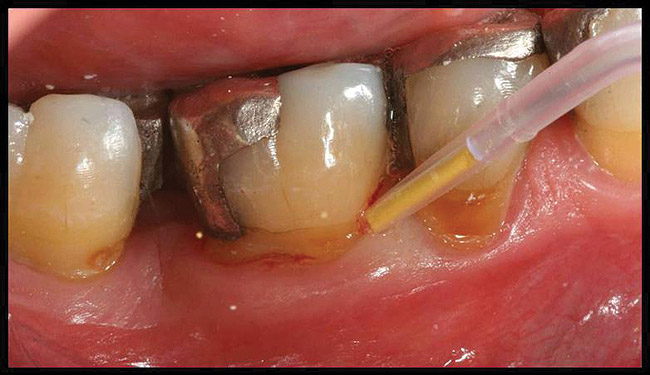

After complete management of moderate to severe periodontitis, including scaling and root planing and in some cases periodontal surgery, subsequent regular periodontal maintenance is reported to prevent tooth loss in up to 85% of patients over a long-term follow-up interval of up to 53 years.6,8 This high success rate of periodontal treatment is comparable to that of dental implants in replacing teeth lost to severe periodontal diseases, highlighting the predictability of maintaining the natural dentition in most patients with periodontal diseases9,10 (Figure 1A and Figure 1B).

Figure 1a  Long-term results of a case involving a 55-year-old woman treated by regenerative periodontal surgery followed by periodontal maintenance every 3 months for 8 years. (A) Radiograph taken in May 2000

Figure 1a